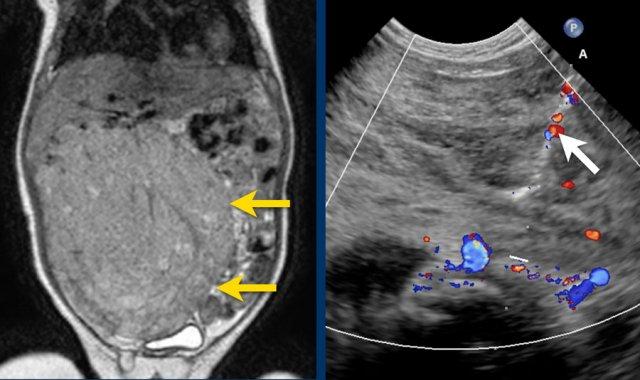

Siêu âm của một bé trai mười lăm tháng tuổi, ban đầu được nghi ngờ có khối u ở thận trái.

Siêu âm cho thấy một khối u nằm kề cực trên phía trong của thận trái. Khối u có vẻ tách biệt với thận. Khối u rất không đồng nhất và có nhiều vôi hóa.

Những phát hiện này phù hợp với u nguyên bào thần kinh hơn là u nguyên bào thận.

Mức độ lan rộng của khối u được đánh giá rõ ràng trên chuỗi xung TSE T2 weighted 3D theo mặt phẳng axial.

The left kidney is compressed and displaced caudally.

Có di căn hạch bạch huyết cạnh động mạch chủ (mũi tên vàng nhỏ).

Nguyên ủy của thân tạng và động mạch mạc treo tràng trên bị khối u bao quanh (đầu mũi tên).

Tĩnh mạch chủ dưới bị đẩy ra phía trước (mũi tên xanh).